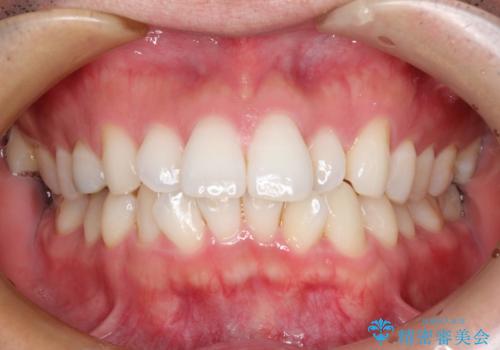

インビザラインで前歯のがたつきを目立たずに矯正治療